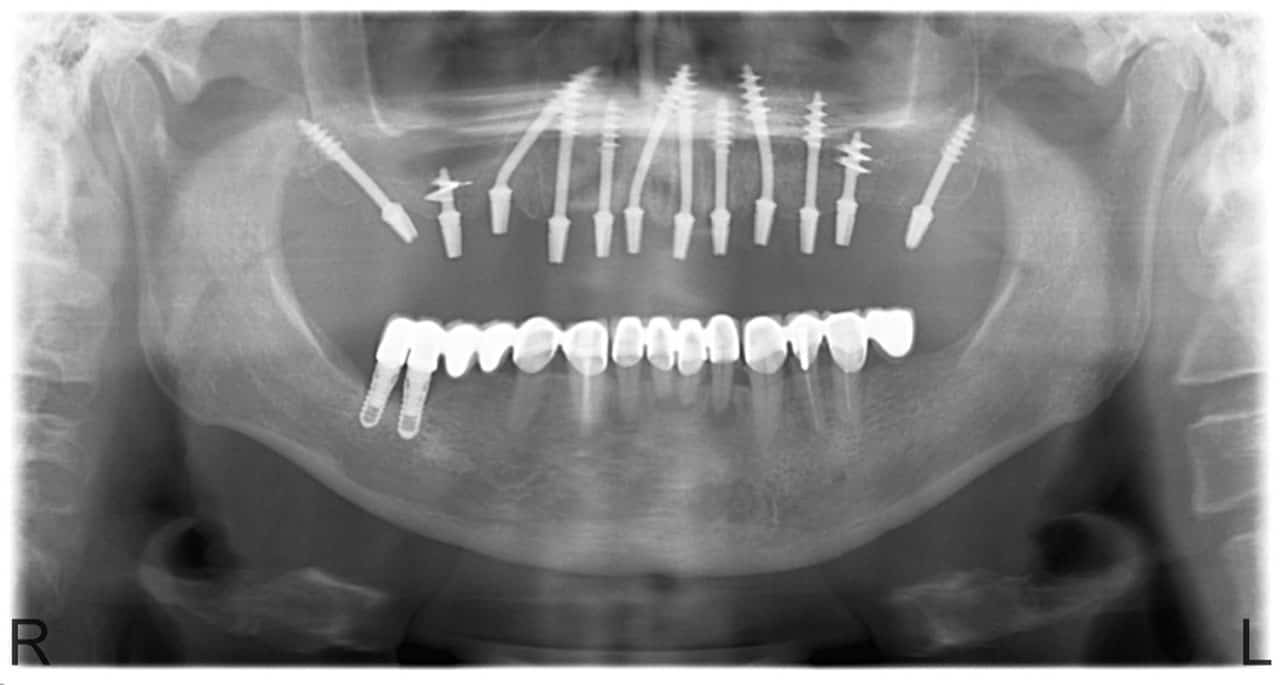

Miből készül a fog implantátum?

Egy fontos lépés megtételére határozta el magát és szeretné, ha a mosolya fényesen csillogna? A fog implantátum beillesztése előtt fontos rendbe hozni a szájüreg állapotát. Ez általában az egyes rágószervek kezelését és a vérző ínytől való megszabadulást foglalja magában.

Ezen felül hangsúlyos, hogy rendszeresen látogasson el a fogorvosához, és bizonyos időnként gondosan ellenőrizze a szájhigiéniáját. A fog implantátumok általában legalább 10–20 évig szolgálják a tulajdonosokat. Az élettartam a páciensek szájüregének megfelelő gondozásától, az egészségi állapotától, a beültetés minőségétől és a behelyezett mesterséges szövet elhelyezkedésétől függ.

Az elülső rágószerveket helyettesítő komponensekre kevesebb rágási terhelés nehezedik, mint a hátsó területén elhelyezkedőkre, ezért ezek hosszabb ideig tartanak. A fog ​​implantátum teste titánból vagy egy arra alapuló ötvözetből készül. A titán rendelkezik a legnagyobb korróziógátló tulajdonságokkal a fémek közül, és egy a testünkkel biológiailag összeegyeztethető anyagról van szó.